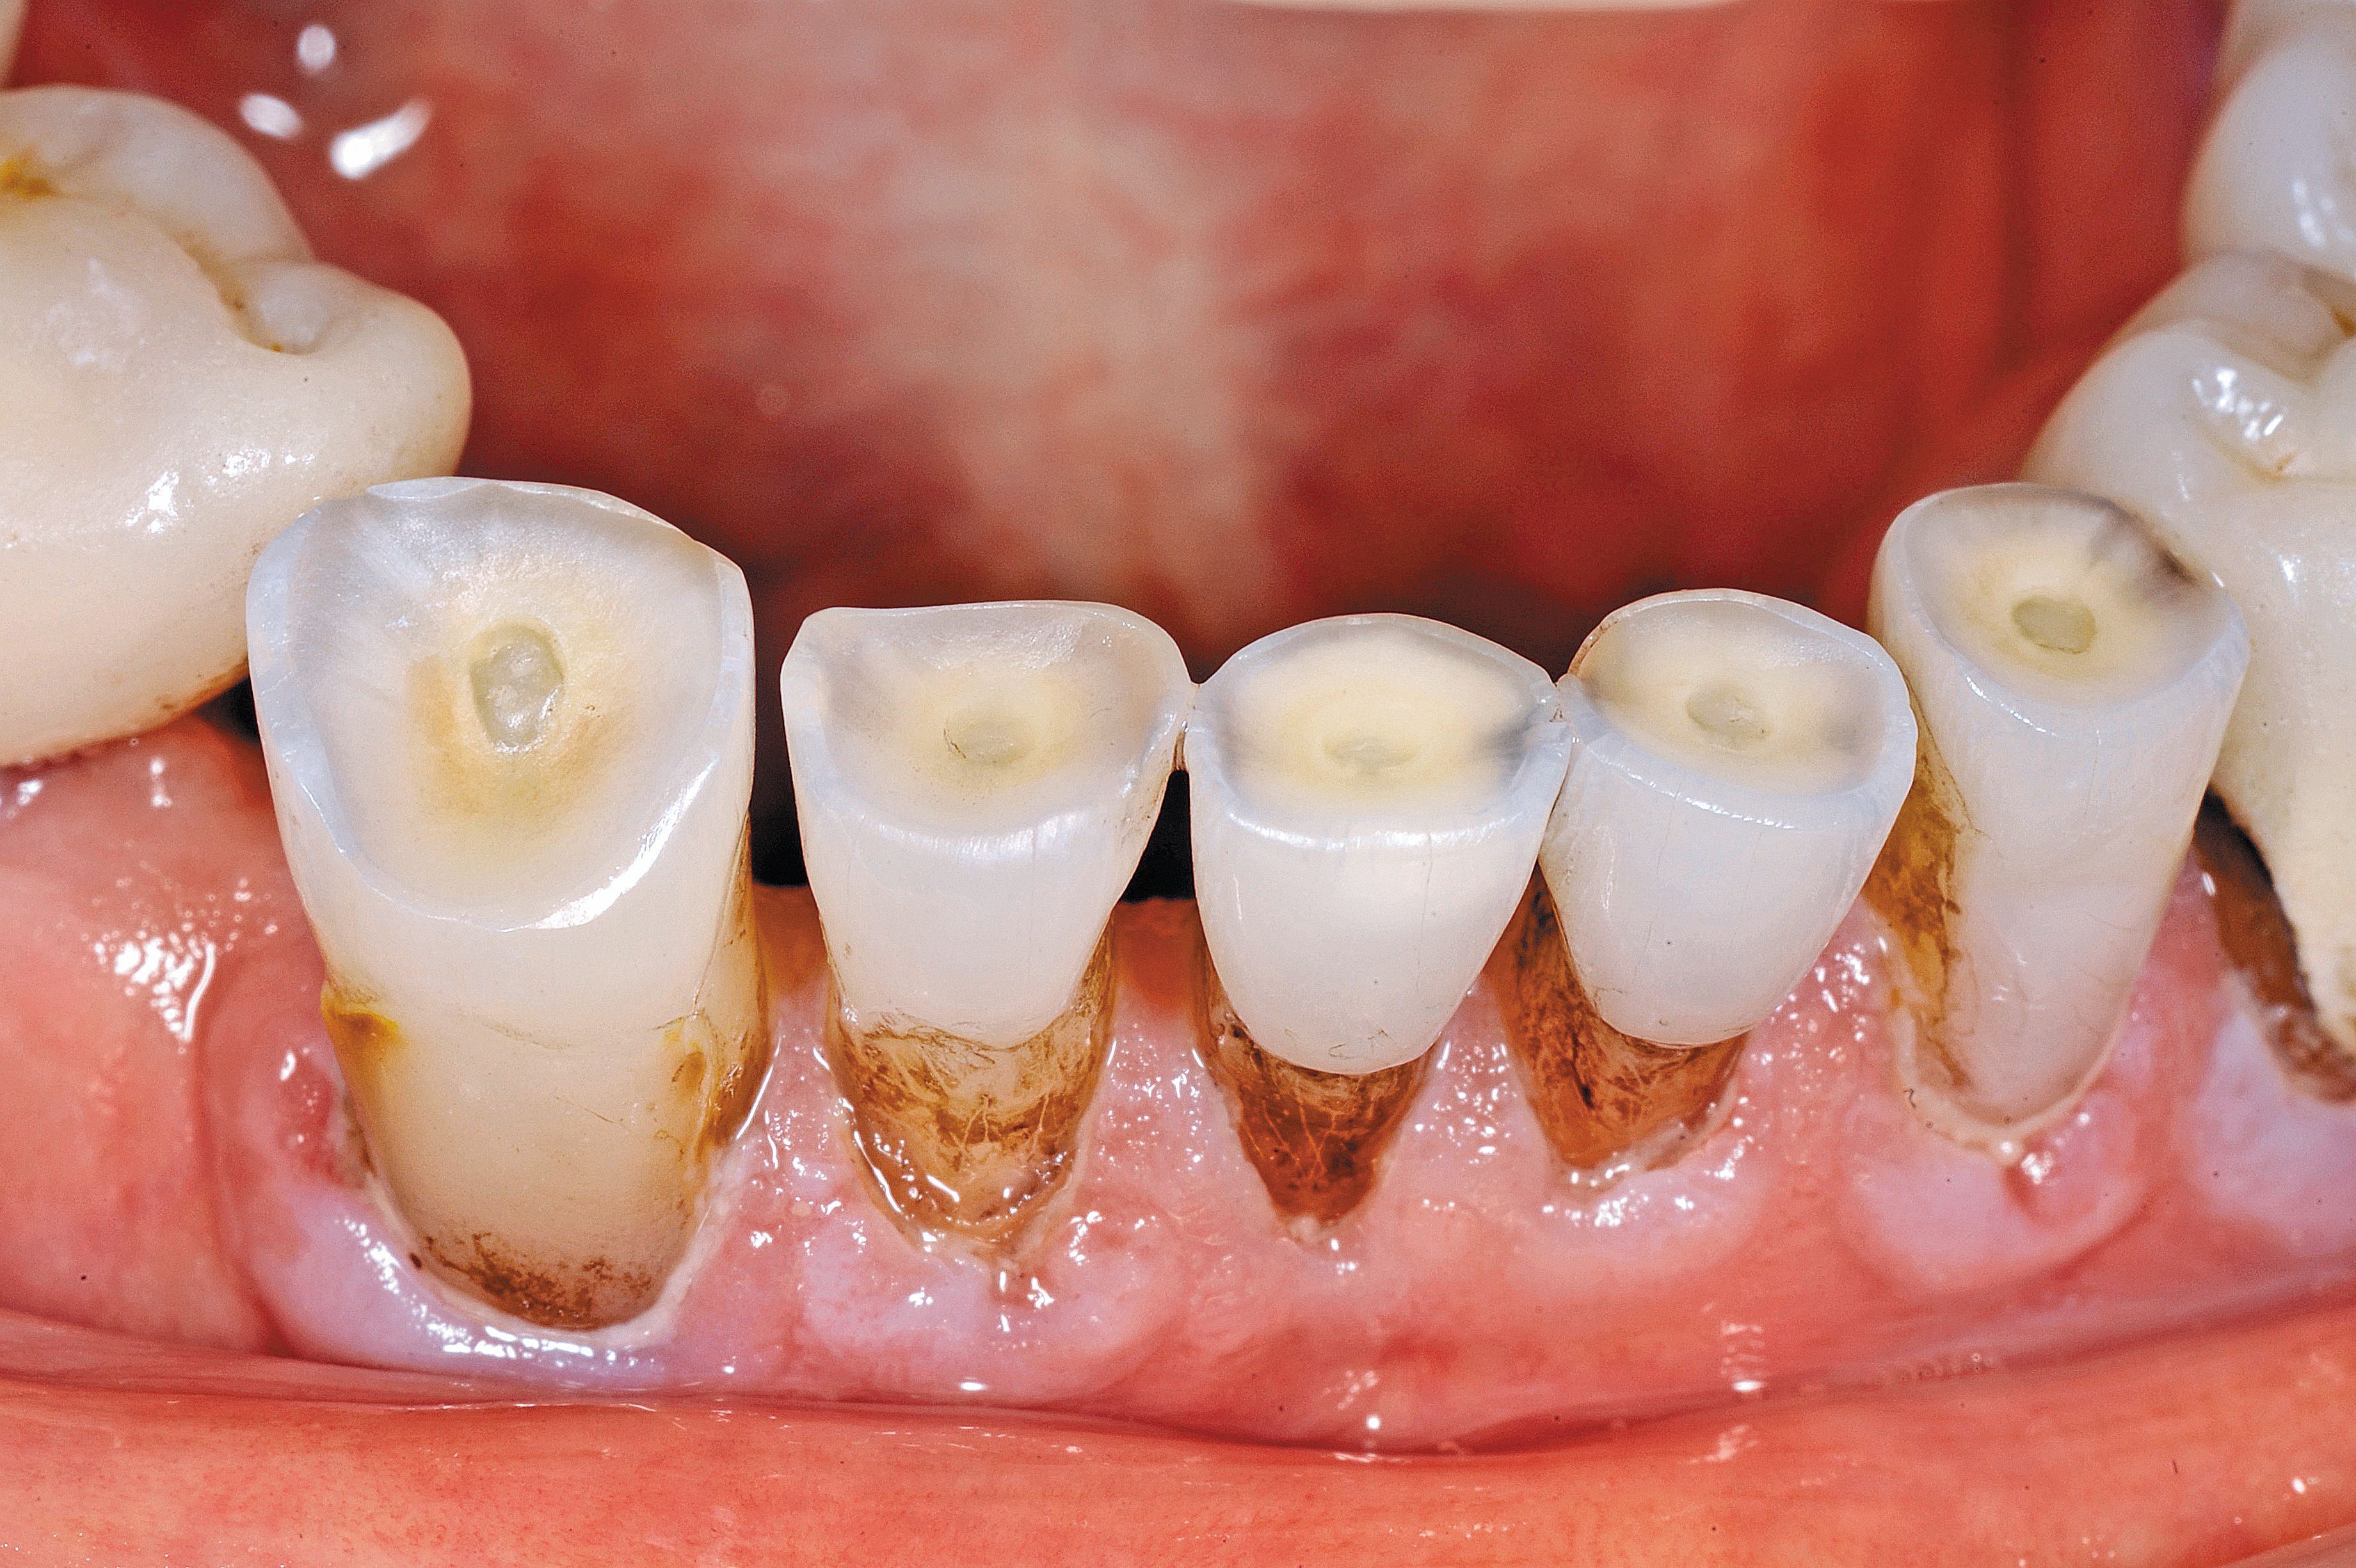

Fig. 1

In this case, the elderly gentleman had worn an upper denture for more than 50 years and was experiencing sensitivity to touch on the incisal edges of tooth Nos. 26 and 27. There was cold sensitivity on the lower incisor abfraction areas as well. There was also recurrent decay around the facial composite on the lower right bicuspid. He has been a chlorhexidine rinse user twice a day for more than 10 years, and staining was an ongoing issue (Fig. 1).